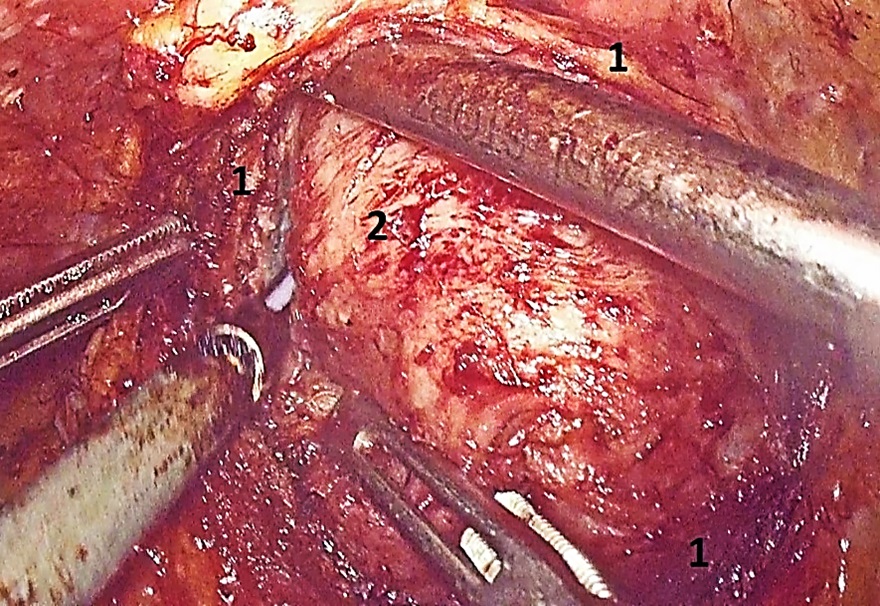

Введение. Лапароскопическая аденомэктомия является методом выбора в лечении гиперплазии предстательной железы (ГПЖ) крупных и гигантских размеров. Данный метод отличается эффективной коррекцией инфравезикальной обструкции, низкой частотой геморрагических осложнений и инконтиненции, уменьшением сроков послеоперационного восстановления, а также повышением качества жизни пациентов.

Материалы и методы. В основу данного ретроспективного исследования включены результаты лечения 36 пациентов, которым была выполнена лапароскопическая трансвезикальная аденомэктомия по поводу ГПЖ. Критерии включения пациентов в исследование: объём предстательной железы свыше 80 см3; показатель максимальной скорости потока мочи ниже 15 мл/с; отсутствие инфекции нижних мочевых путей, нейрогенных расстройств мочеиспускания и трансуретральных оперативных вмешательств в анамнезе. Всем исследуемым пациентам выполняли цистометрию (наполнения и опорожнения) непосредственно до операции и через 3 – 6 месяцев после.

Результаты. Средний возраст больных составил 65,8 ± 4,21 года. Средний объём предстательной железы был равен 148,5 ± 17,9 см3, среднее значение суммарного балла симптоматики заболевания по шкале IPSS перед началом лечения — 19,4 ± 2,3 балла. Максимальная скорость потока мочи колебалась от 3,2 до 11,3 мл/с и в среднем составила 6,2 ± 1,6 мл/с. В раннем послеоперационном периоде ни у одного из исследуемых пациентов не отмечено осложнений тяжелее I степени по классификации Clavien-Dindo. После операции было отмечено статистически значимое снижение показателя детрузорного давления с 20,29 (± 2,9) до 11,24 (± 2,9) см вод. ст., а также увеличение максимальной скорости потока мочи с 6,24 (± 1,61) до 25,1 (± 5,05) мл/с.